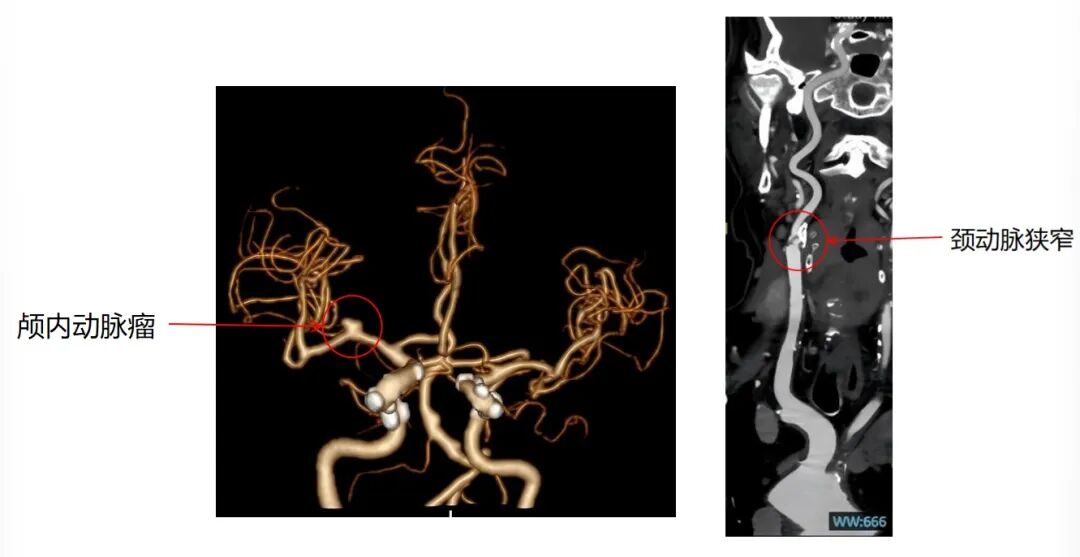

患者曾出现过短暂性脑缺血等症状,伴有血管内微小血栓脱落,情况危急。入院检查后发现,其右侧脑部血管中,藏着两处隐患:右颈内动脉起始部重度狭窄伴不稳定斑块,狭窄程度达70%,随时可能引发急性脑梗死。同时,患者同侧颅内还有一个不规则动脉瘤,存在破裂出血的致命风险。

术后影像资料